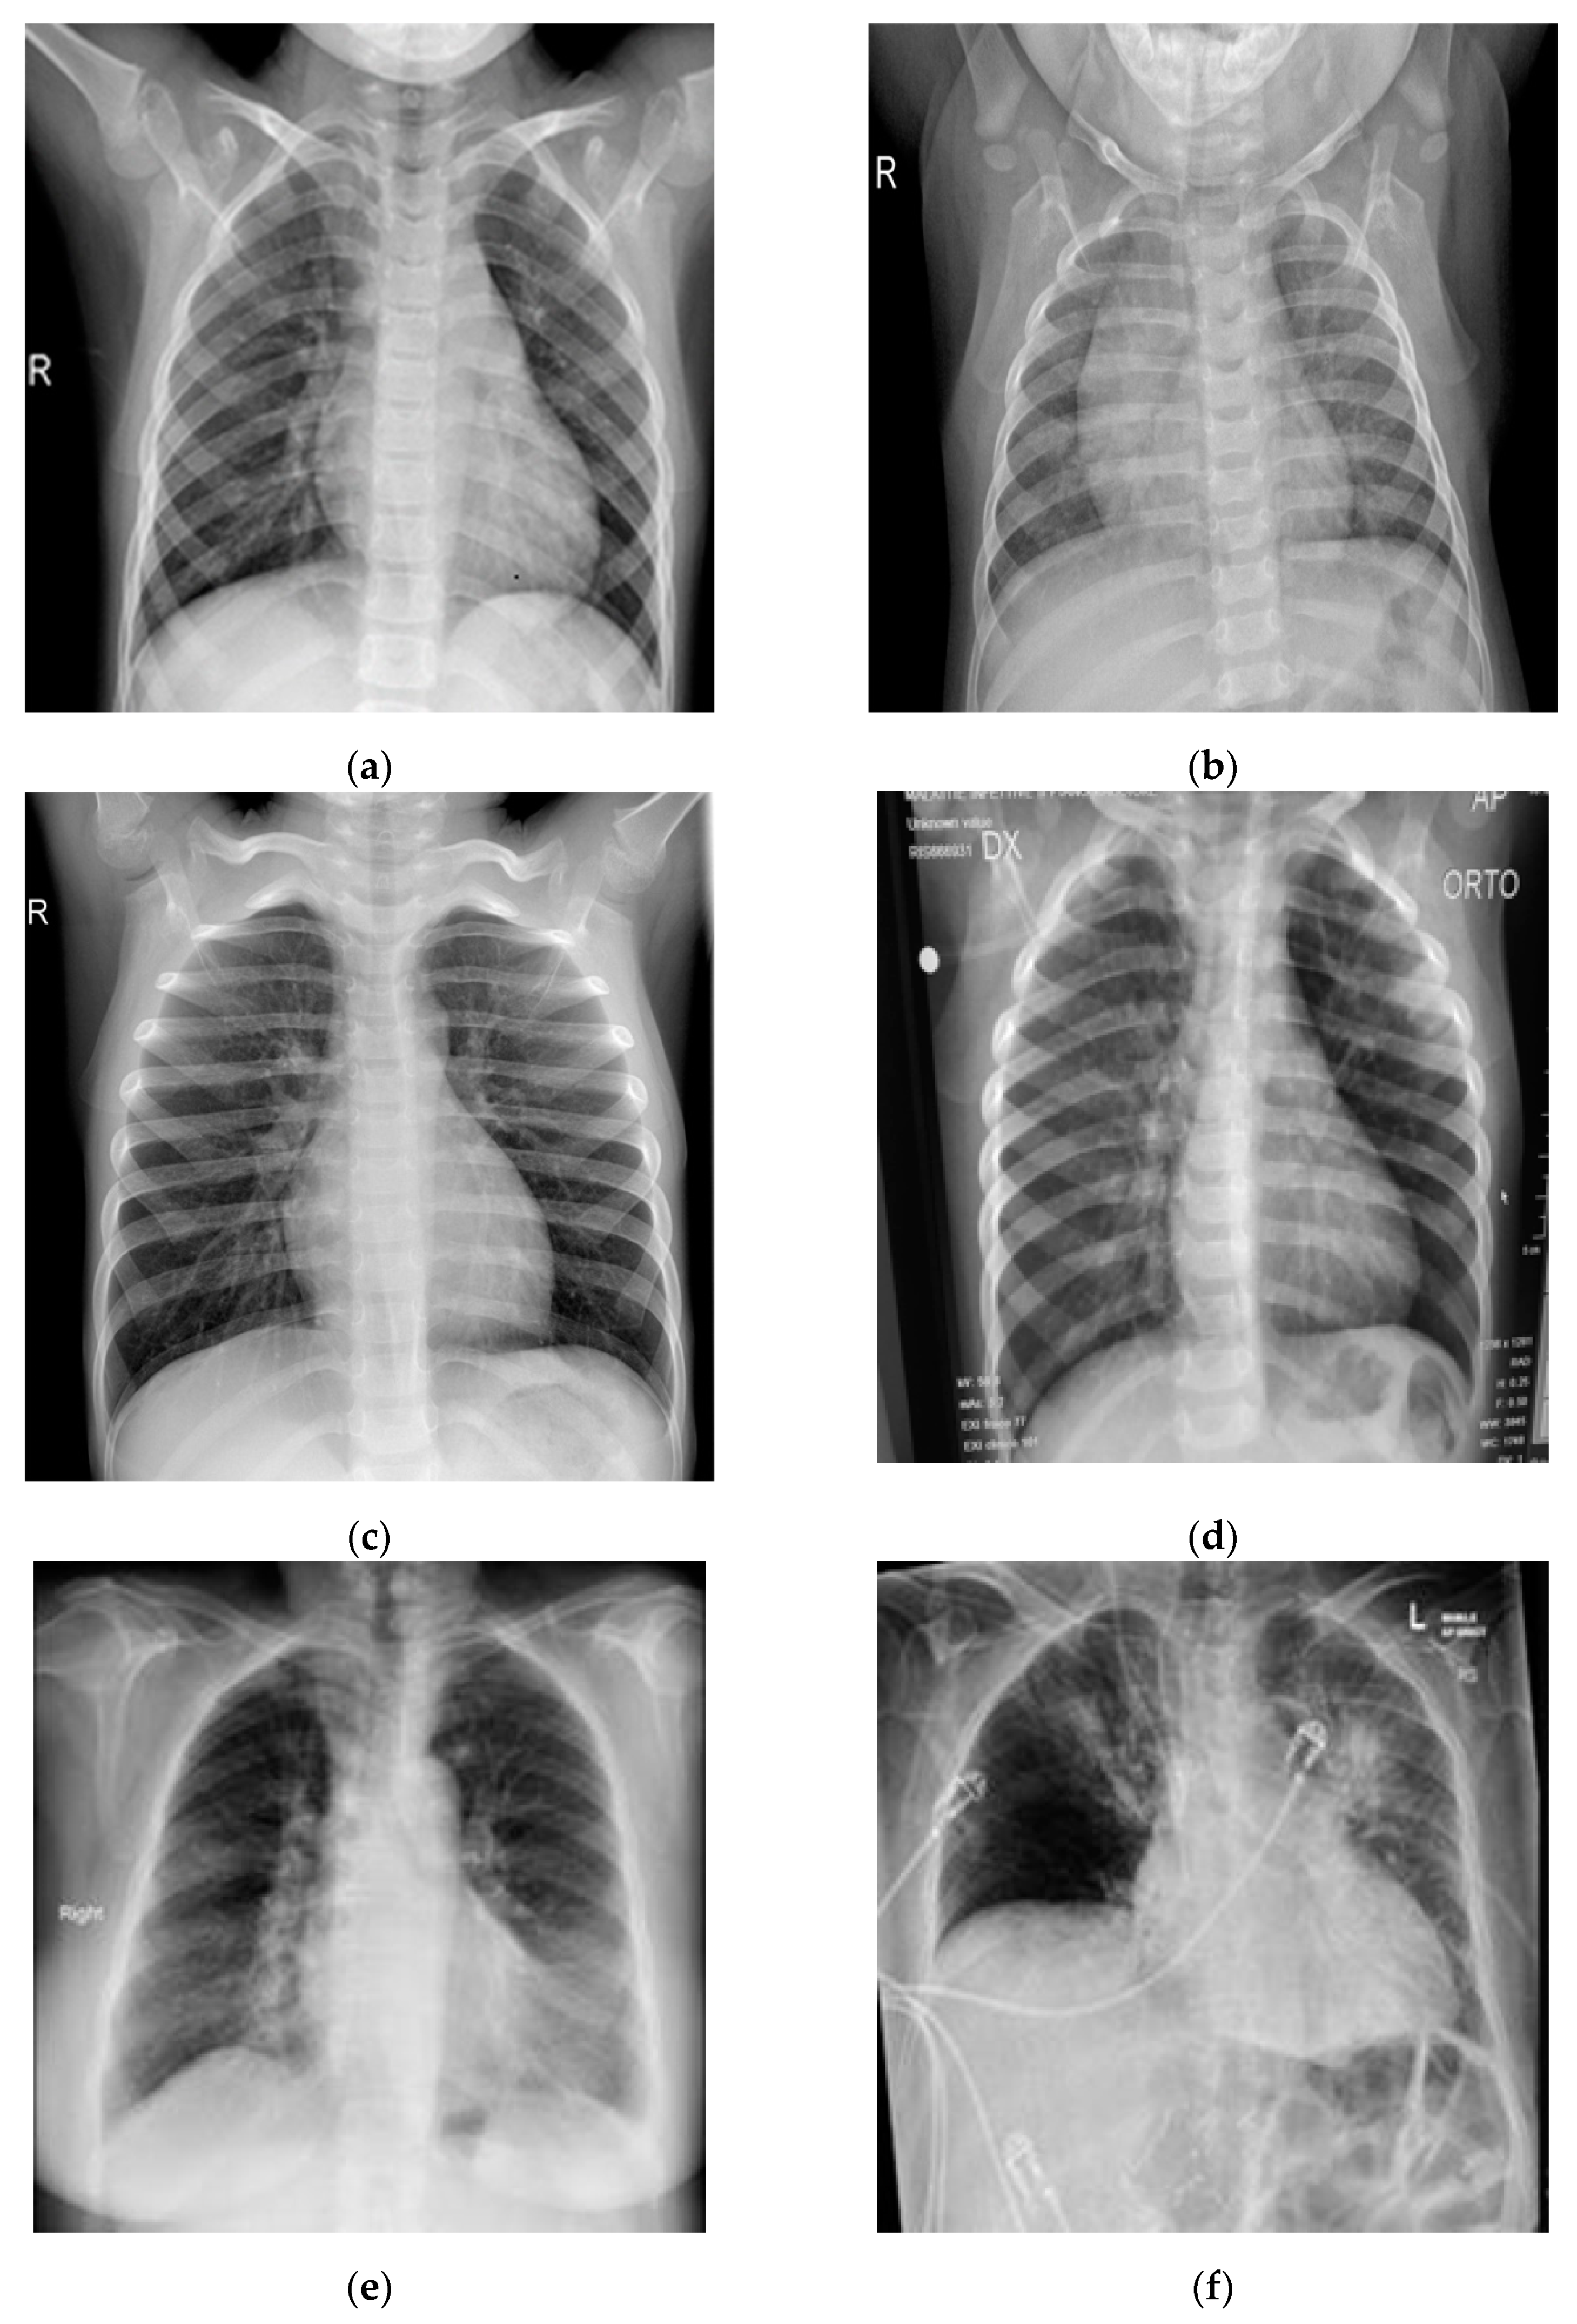

In this study, pulmonary (chest) X-ray images were used for the diagnosis of COVID-19. The dataset was categorized into two main classes, i.e., COVID-19 and normal. A total of 7232 images (3616 COVID-19 + 3616 normal) were accessed from the ‘COVID-19 Radiography Database (available at Kaggle, https://www.kaggle.com/tawsifurrahman/covid19-radiography-database, accessed on 4 May 2021) [30]. From the total images, 70% (5062 images) were used for training + validation, and the remaining 30% (2170 images) were used for testing purposes. The training + validation dataset of 5062 images was further split into a 70:30 ratio, i.e., 3544 (70%) images for training purposes and 1518 (30%) images for validation purposes. The details of the data splitting are given in Table 1. In addition to the dataset accessed via Kaggle, another locally collected dataset of 450 images (COVID-19 + normal) was also used for testing and prediction purposes. This indigenous data of chest X-ray images of Pakistani COVID-19 positive and normal patients have been collected from a local hospital. The samples of normal and COVID-19 X-ray images assessed via the Kaggle database are shown in Figure 1, whereas the samples of the locally collected images are given in Figure 2.

Figure 2.

Samples of local Pakistani verified dataset used for the testing of trained models: (a–c) COVID-19 chest X-rays; (d–f) normal chest X-rays.